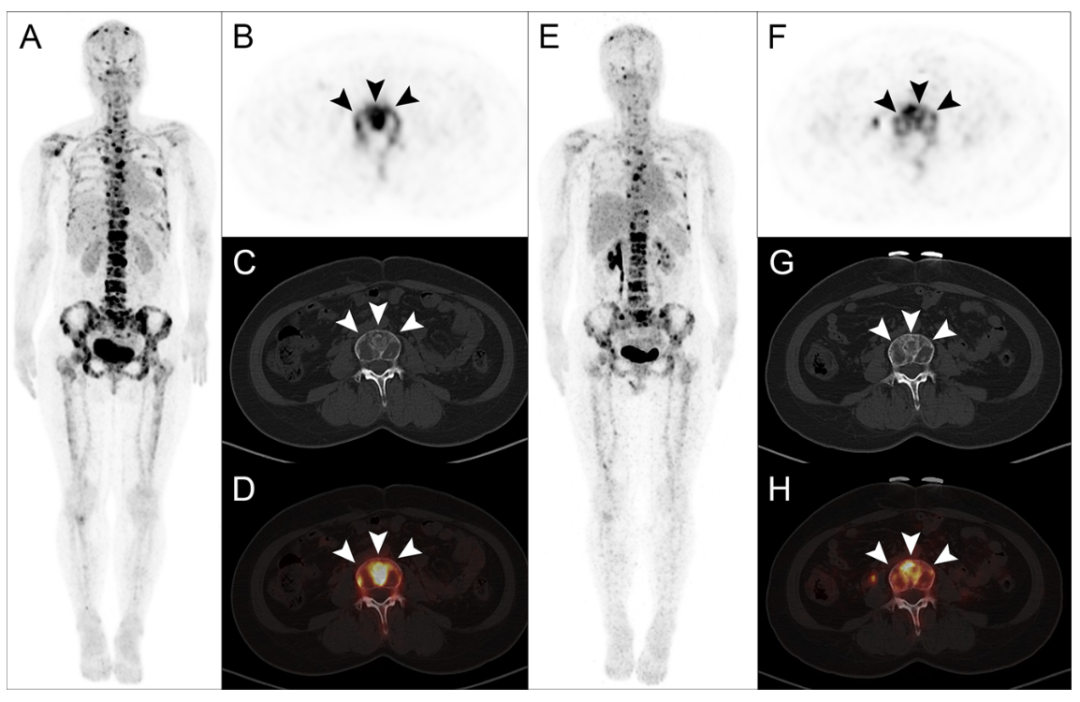

一位33歲的乳腺癌骨轉移患者在接受了1850 MBq的177Lu-DOTA-IBA治療后,其疼痛癥狀在短短一周內便得到了完全緩解,而其Karnofsky表現狀態(KPS)評分也在兩周后升至100分。在治療后的8周隨訪中,通過68Ga-DOTA-IBA PET/CT影像復查發現,該患者的骨轉移病灶示蹤劑攝取量顯著下降,SUVmax值從治療前的高水平降至10.2,綜合影像學與臨床表現,該患者的治療效果被評定為部分反應(PR),這一結果印證了177Lu-DOTA-IBA在緩解疼痛、提升生活質量方面的卓越能力,彰顯了其在促進骨轉移病灶修復、改善患者預后方面的巨大潛力。